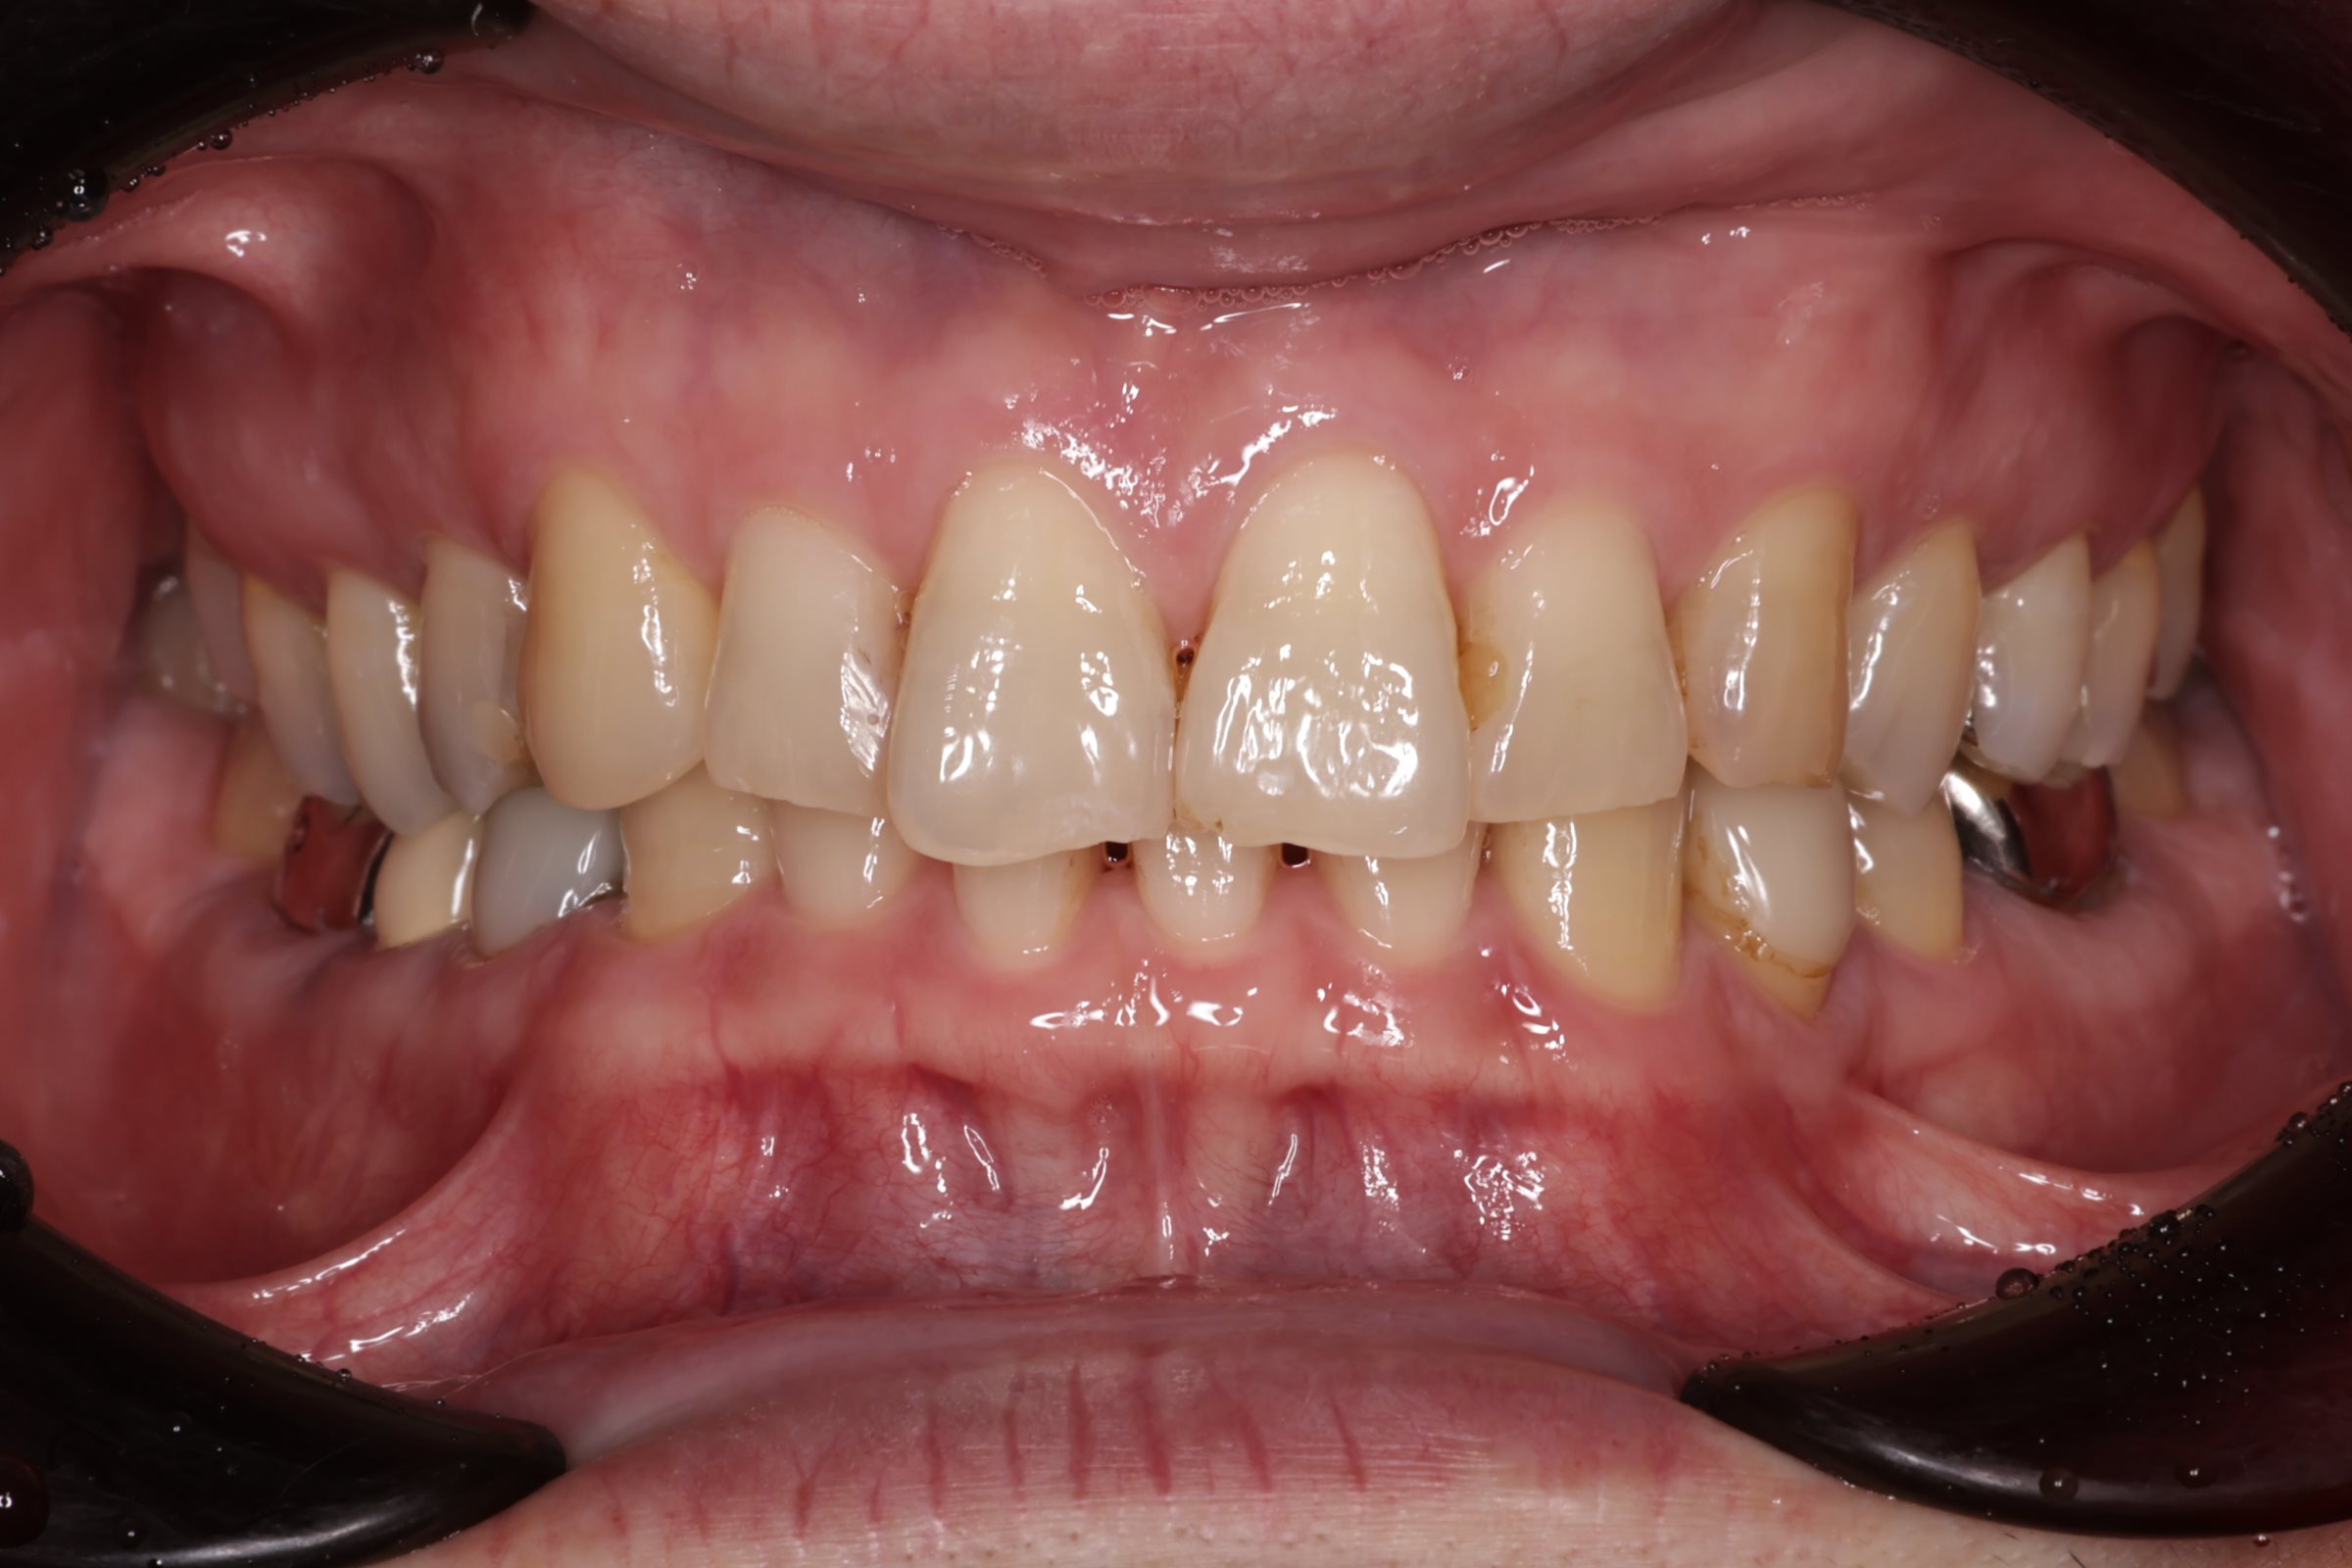

治療結果

全ての金属を非金属素材に置き換え、感染源も除去した結果、治療後は症状が落ち着いている状態が確認されました。 患者様はアレルギーやそれに伴う症状の悩みが大幅に軽減されたようで、非常に喜んでいただけました。

本症例では、金属アレルギーの懸念に加え、古い金属修復物の下に潜んでいた虫歯や感染源を全て取り除き、生体親和性が高く審美性にも優れた非金属素材に置き換えることができました。

After